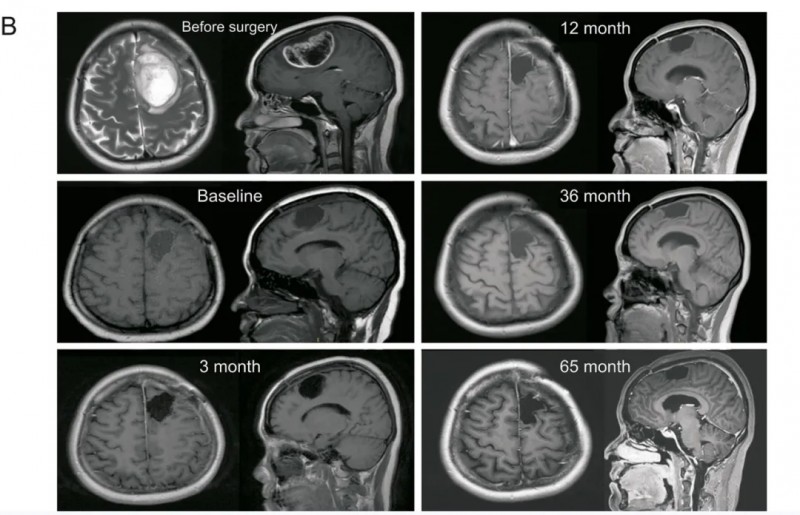

结果显示:患者每三个月行MRI检查监测病情,每三次疫苗接种后7-10天抽取外周血监测免疫反应。术后即刻Karnofsky功能状态评分(KPS)为70分,言语及词语寻找困难症状逐步缓解;术后一年KPS评分达90-100分,生活恢复正常;2022年11月MRI检查未发现复发迹象(详见下图)。

▲图源“J Pharm Anal”,版权归原作者所有,如无意中侵犯了知识产权,请联系我们删除